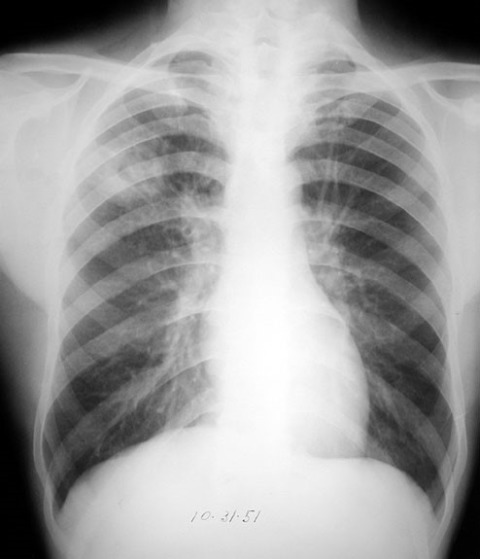

Ini ada kasus pasien menarik nih! Laki-laki, 35 tahun, tanpa keluhan, dilakukan rontgen thoraks saat medical check up untuk melamar pekerjaan.

Ditemukan gambaran sebagai berikut :

Menurut dokter semua, apakah kemungkinan diagnosis banding pasien ini?

tampak corakan broncovesikuler yang meningkat paracardial jika tanpa keluhan bisa jadi karena pasien merokok

tampak gambaran seperti coin di regio paru dextra lobus superior. kesan infeksi jamur, cavitas TB paru, abses paru dan massa. dipertegas corakan nya meningkat di lobus superior. kesan ada TB sebelumnya?

mungkin bisa dipastikan dengan perkusi dan auskultasinya bagaimana ya dok. serta anamnesis riwayat medis sebelumnya.

pertimbangan VCT sepertinya bisa.

saran bisa lakukan ro. thorax lateral untuk menghilangkang curiga masa.

halo TS semua, setuju dengan dr Jeffry, usul untuk dilakukan CT scan thorax saja agar dapat terlihat dari paru dan mediastinumnya